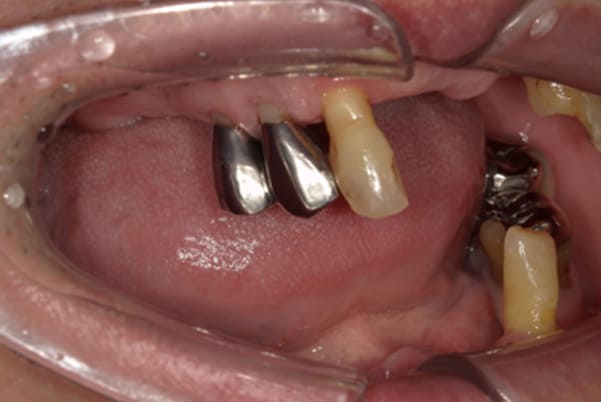

歯周炎により歯が多く抜けた状態で咬めるところがほとんどない状態でした。

検査の結果、上の歯3本は何とか残せる状態で、ご本人もできるだけ歯は抜きたくないとのご希望であったため、残せる歯もそのままバネをかけると負担が大きく数年で抜歯となる可能性が高いため、ご自身の歯に磁石を装着することで歯を長持ちさせ、入れ歯も外れにくい入れ歯にしました。

ご自身の歯を抜かず、磁石を装着することで、歯への負担を減らし、入れ歯も外れないような設計としました。

プラスチックの入れ歯は、強度がないため厚くなり違和感がでやすいこと、熱を通しにくく食べ物の熱が伝わりにくい、壊れることがあることが欠点のため、患者様の生活習慣やご希望をお聞きし、上顎には金属を用いることで、プラスチックの1/3程度の厚みとなり、温かい食べ物や冷たい食べものの熱をお口で感じ、丈夫な入れ歯の設計としました。

上顎に金属は用いていますが、外観に触れないため、機能性と審美性を持ち合わせた自然な口元になりました。